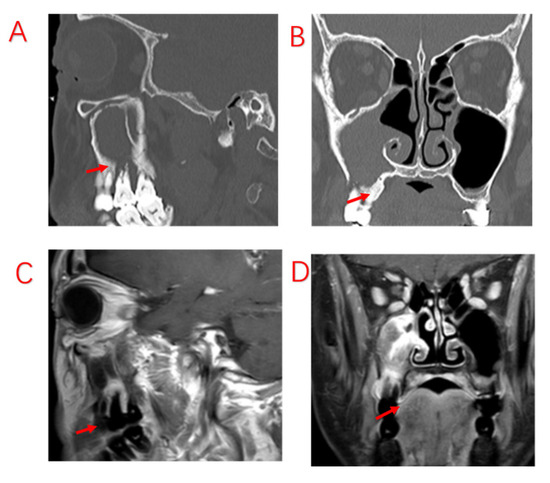

Figure 1.

A patient with odontogenic sinusitis due to EPL with bone defects in the MSF. (A): Sinus CT shows resorption of alveolar bone on the palatal side of the left upper first molar, forming a narrow and deep periodontal pocket. (B): MRI shows diseased tissue in the periodontal pocket connected to swollen mucosa in the maxillary sinus. (C): Bone penetration of the palatal MSF in the extraction socket is observed during surgery. Red arrows indicate bony defects in the MSF.